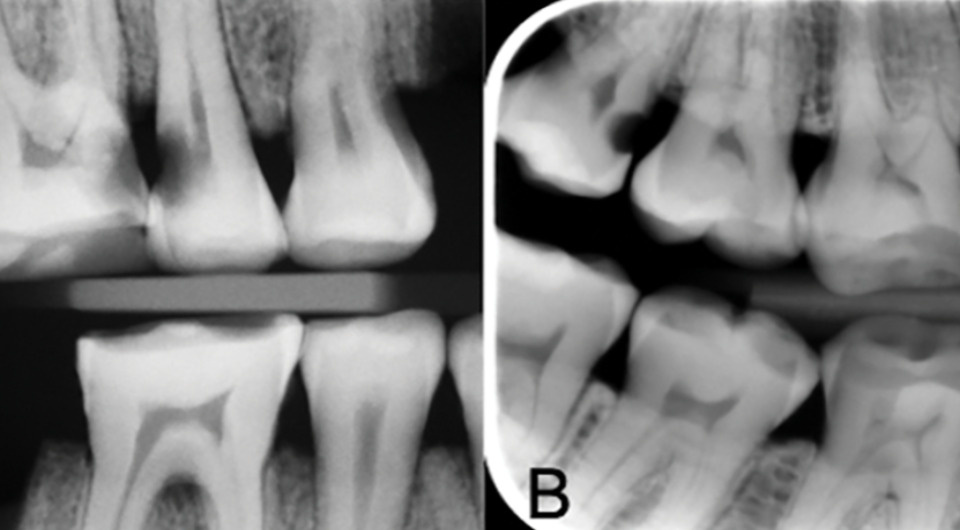

Палеопатологи исследовали останки 171 человека, живших в X–XII веках нашей эры, которые обнаружили во время раскопок в некрополе у Варнхемского монастыря. Почти у половины (49 процентов) обследованных людей ученые обнаружили хотя бы одно кариозное поражение, причем эти стоматологические заболевания встречались только у взрослых. Помимо патологий на зубах некоторых скандинавов исследователи зафиксировали свидетельства манипуляций: стачивания, ковыряния зубочистками и лечения. Об этом сообщается в журнале PLoS One.